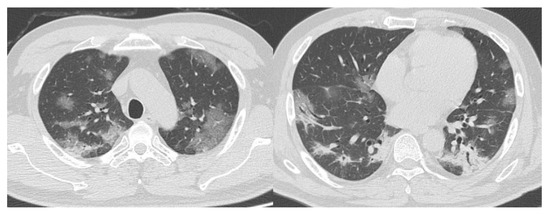

- CO-RADS 5 means a very high level of suspicion for pulmonary lesion resulting from COVID-19, based on typical CT findings. Obligatory features are ground-glass opacities, with or without consolidations, close to visceral pleural surfaces, including the fissures, and a multifocal bilateral distribution.